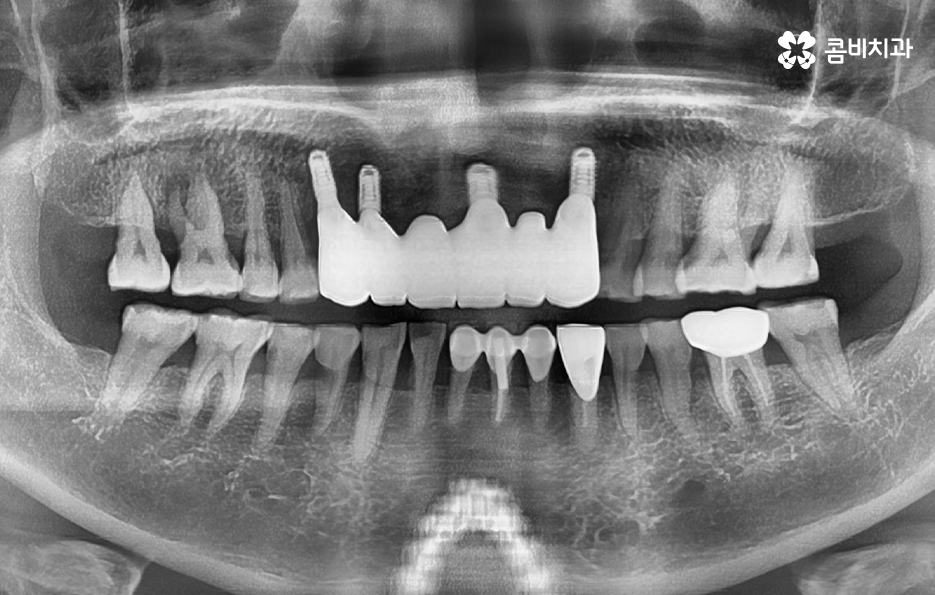

따라서 앞니임플란트를 해야하는 경우에는 치아를 잃게 될 경우 곧 바로 치료를 하는 것이 중요하며 임플란트의 수명과 심미성을 위해서도 치아를 잃은 개수만큼 치료하는 것을 권장하고 있는데요.

자연치아의 경우 치주조직이 치아를 감싸고 있는 구조라면 임플란트 치료 후에는 시간이 지날수록 어느정도 잇몸이 퇴축되는 것을 감안해야 하기 때문에 앞니임플란트 치료 후 심미성에 있어서도 잇몸라인의 보존을 위한 빠른 치료는 앞니에 특히 중요하다고 볼 수 있어요

아무래도 잇몸이 내려앉게 될 경우 임플란트의 보철물이 길어 보이게 될 수 있고 잇몸은 한번 내려 앉으면 회복이 어렵기 때문에 초기에 잇몸을 최대한 보존하면서 치료하는 것이 중요한 거예요.

종합하면 앞니 치료에 있어서는 앞니의 기능적인 특성상 음식을 끊는 역할도 하고 웃을 때 앞니가 위주로 보이기 때문에 심미적인 면을 함께 고려하여 치료 계획을 세울 필요가 있는데요

잇몸 상태와 전신 건강이 양호한 경우에는 원데이임플란트를 통해 앞니임플란트 치료를 많이 진행하지만 오늘 케이스처럼 이미 치아를 발치한 후 시간이 지난 경우나 치주염으로 인해 잇몸 뼈가 녹고 염증이 심한 경우에는 빠른 치료보다는 잇몸을 충분히 회복하여 건강하고 안전한 결과에 더 초점을 두고 있는데요.

각 개인에 따라 치료 계획은 1:1 맞춤형으로 진행되고 있으며 임플란트는 치료를 잘 받는 것과 함께 사후 관리를 잘하여 오랫동안 문제없이 수명을 잘 유지하는 것에 더욱 초점을 둬야하기 때문에 치료 시점 뿐 아니라 치과 선택에 있어서도 잘 따져보실 필요가 있어요